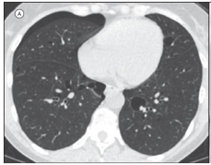

Imagem 1: Pneumonia intersticial linfocítica